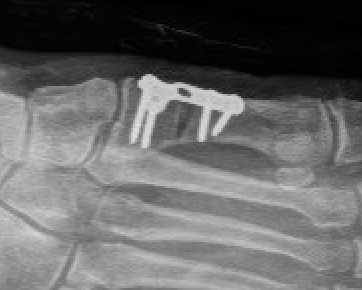

Triple Arthrodesis

www.boneschool.com/triple-arthrodesis

Aim

Realign hindfoot with plantigrade foot

Technique

Lengthen tendoachilles - gastrocnemius recession / release

Lateral approach to subtalar and CCJ / medial approach to TNJ

Remove articular cartilage and prepare joints for fusion

Reduce joints

- Grice maneuver - laminar spreader between anterior process of calcaneus and talus

- check subtalar joint alignment - slight valgus / not neutral or varus

- may need to add medial slide calcaneal osteotomy

Fuse TNJ first to align STJ

Fuse STJ

- may need large lateral bone wedge

- may have issues with lateral skin closure

Fixation - screws / plates / staples

+/- medial osteotomy to allow medial metatarsal weight bearing

- Cotton osteotomy (cuneiform) / first metatarsal osteotomy